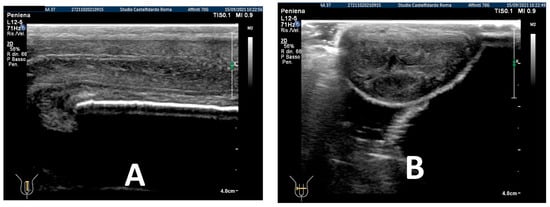

After the completion of the third treatment cycle, and after 2 years and 9 months (33 months), the patient underwent follow-up with a physical exam and a penile Doppler ultrasound. At follow-up, the IIEF score was 28. The penile pain was no longer present. We then observed an absence of penile deformation. The ultrasound examination no longer showed any plaque (Figure 8).

Figure 8. Ultrasonography of the penis after the 3rd therapy cycle. (A) Longitudinal view; (B) axial view.